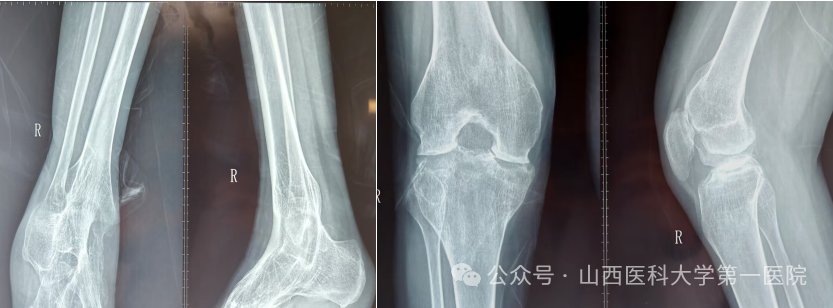

一名42岁的强直性脊柱炎患者,多年来饱受病痛折磨。随着病情进展,双侧髋关节逐渐“锈死”,无法弯腰、下蹲,甚至连坐下都成了奢望——吃饭只能站着,休息只能躺着,生活自理能力几乎丧失。接诊后,骨科杨自权主任团队对患者进行全面检查,发现患者不仅脊柱强直呈“板状腰”,双侧髋关节出现严重融合,而且双膝、双踝关节功能明显下降,手术难度极大。

强直性脊柱炎伴髋关节病变的置换手术,被誉为骨科领域的“硬仗”。杨自权总结此类患者三大诊疗难点:一是麻醉困难,患者脊柱强直,常无法配合常规麻醉体位;二是解剖变异,长期炎症导致关节周围骨质疏松、肌肉萎缩,手术视野不清,风险极高;三是对手术精度要求更高,假体安放的位置、角度稍有偏差,就会影响术后关节稳定性及使用寿命。